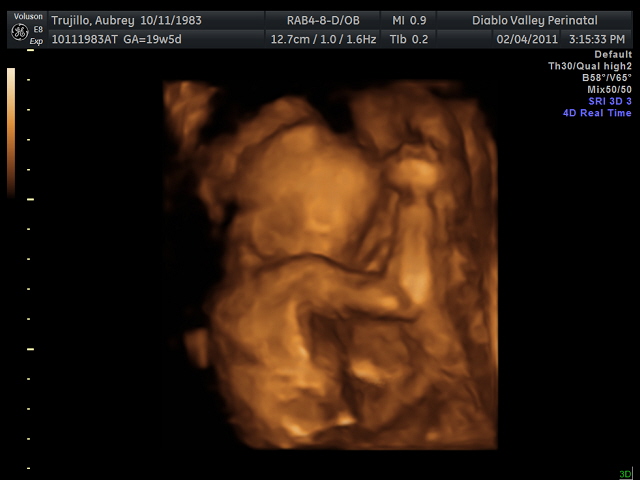

20 weeks - profile20 weeks - Profile again20 weeks - Right foot!20 weeks - sucking thumb!!!!20 weeks - hand near face20 weeks - flexing his bony arms!20 weeks - hiding from mommy and daddy!20 weeks - it's a boy!33 weeks - 3D!33 weeks - 3D!33 weeks - 3D!